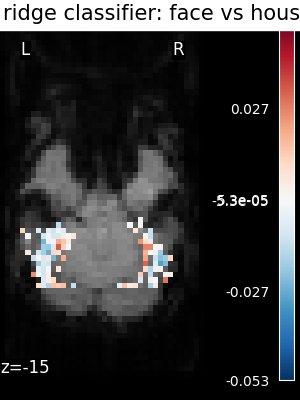

svc(same assvc_l2) : The support vector classifier.svc_l1: SVC using L1 penalization that yields a sparse solution : only a subset of feature weights is different from zero and contribute to prediction.logistic(orlogistic_l2) : The logistic regression with l2 penalty.logistic_l1: The logistic regression with l1 penalty (sparse model).ridge_classifier: A Ridge Regression variant.dummy classifier: A dummy classifier is a classifier that makes predictions using simple rules. It is useful as a simple baseline to compare with other classifiers.

The ridge is fast to fit and cross-validate, but it will not work well on ill-separated classes, and, most importantly give ugly weight maps

The corresponding weight maps (below) differ widely from one estimator to the other, although the prediction scores are fairly similar. In other terms, a well-performing estimator in terms of prediction error gives us little guarantee on the brain maps.